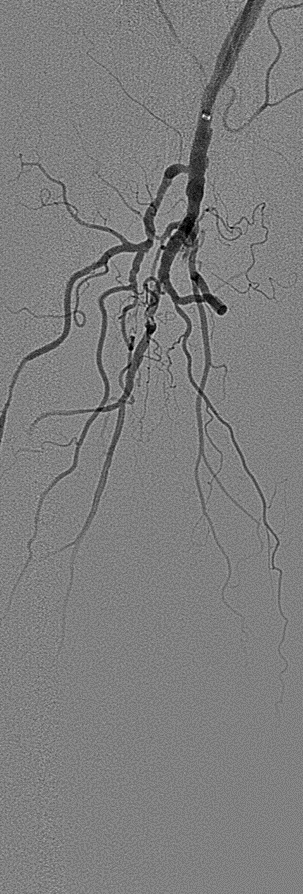

★ Case 1

noproximal stump in SFA,>250mm

★ Case 2

significantdistal collaterals